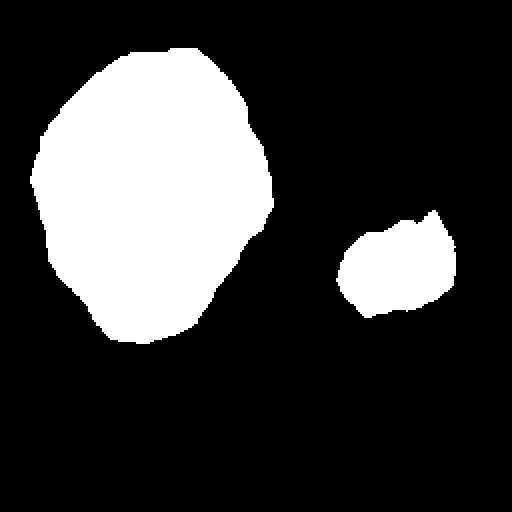

A few sample images and the corresponding masks of the polyp dataset in HyperKvasir are shown in Fig 2. The polyp images are RGB images. The masks of the polyp images are single-channel images with white () for true pixels, which represent polyp regions, and black () for false pixels, which represent clean colon or background regions. In this dataset, there are different sizes of polyps. The distribution of polyp sizes as a percentage of the full image size is presented in the histogram plot in Fig 3, and we can observe that there are more relatively small polyps compared to larger polyps. Additionally, a subset of this dataset was used to prove that the performance of segmentation models trained with small datasets can be improved using our SinGAN-Seg pipeline, and the whole dataset was used to show the effect of using SinGAN-Seg generated synthetic images instead of a large dataset which has enough data to train segmentation models. In this regard, this dataset was used for two purposes:

After training SinGAN-Seg models, we generated random samples per real image using the input scale , which is the lowest scale that uses a random noise input instead of a re-scaled input image. For more details about these scaling numbers and corresponding output behaviors, please refer to the vanilla SinGAN paper [56]. Three randomly selected training images and the corresponding first synthetic images generated using scale are depicted in Fig 4. The first column of the figure represents the real images and the ground truth mask annotated from experts. The rest of the columns represent randomly generated synthetic images and the corresponding generated mask.